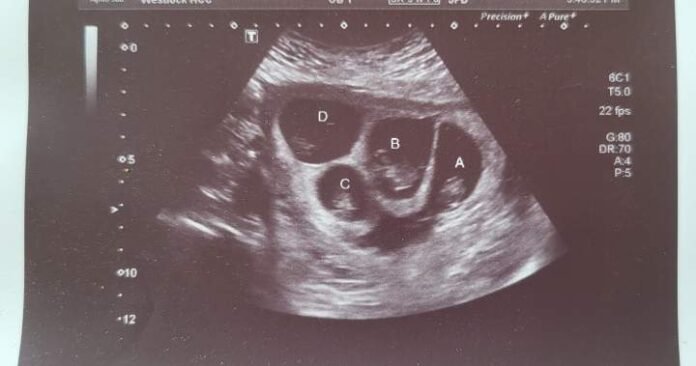

She’s now six months pregnant with quadruplets: three boys and one girl. When she found out, she was in shock.